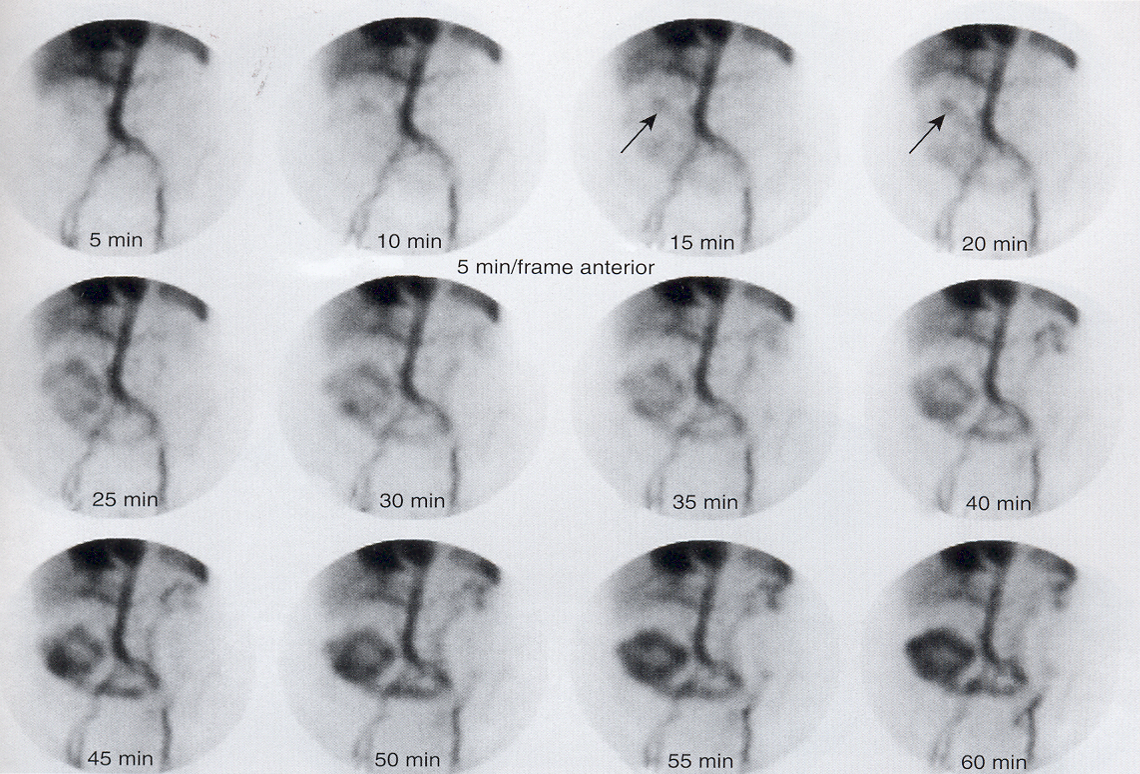

When should we take static images?

every 5-15 min

LAO with single head camera and Anterior and Posterior images with dual head camera

bc the stomach is not just anterior, fundus is posterior and antrum is more anterior

what is this pictuer showing?

a normal gastric image

what is this picture showing?

abnormal-gastroparesis